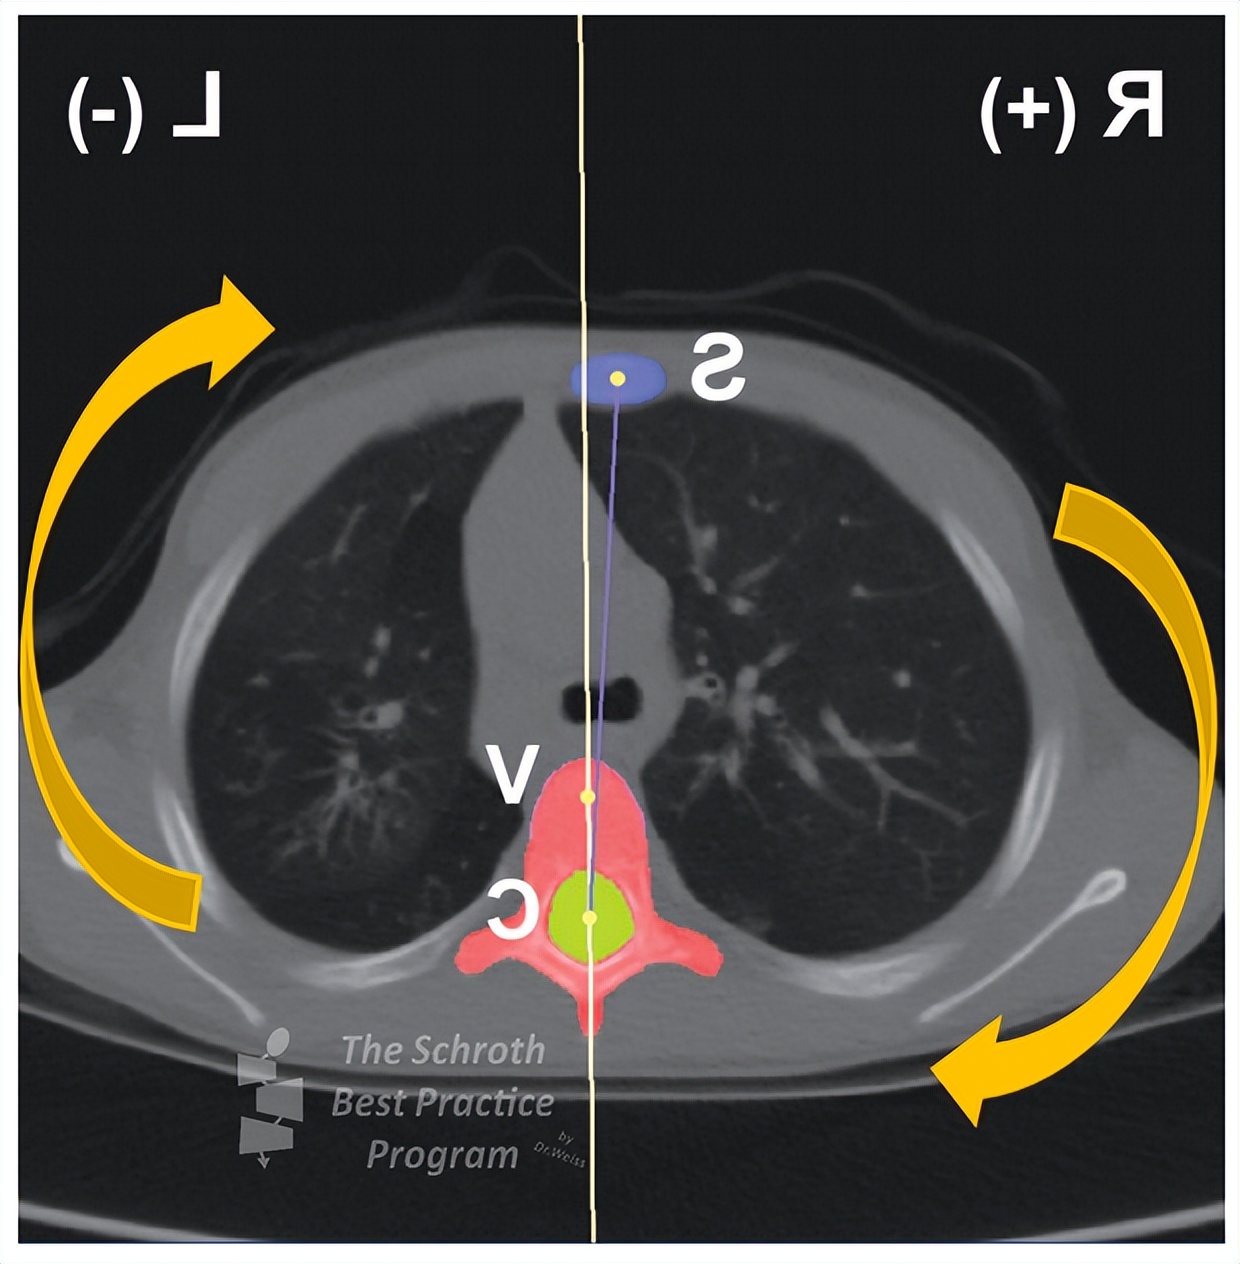

Kouwenhoven等人于2006年发现,即使是没有脊柱侧凸的普通人,在胸椎的第6~8节段有右旋的趋势,右旋角度最大位2°。

早在1984年Dickson就给出了一种可能的解释,在第5到第8胸椎椎体的向右旋转与在该位置的降主动脉及其和心脏的搏动相关。

Kouwenhoven等人(2007)在研究中对37名没有脊柱侧凸但是存在内脏异位的受试者进行了横切面的磁共振检查。内脏异位是一种罕见的、但不属于疾病的现象,即器官在体内另一侧镜面反转。研究发现这些受试者的椎体旋转方向与无脊柱侧凸且器官位置正常的人相反。

所以为什么胸椎侧凸经常发生在右侧,为什么胸椎更容易顺时针旋转?可能和我们的身体内部构造息息相关!